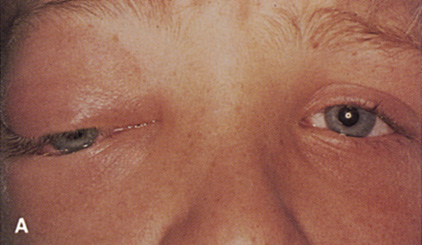

Fig. 6. Lateral orbitotomy through upper eyelid skin crease A. Photo demonstrating right globe ptosis present for more than 2 years. B. Axial CT scan showing a well outlined oval lesion in the lacrimal gland

fossa. C. Coronal CT showing lesion pushing globe inferiorly. D. Skin crease excision marked for lateral orbitotomy. E. Lateral orbital rim exposed. Bone cuts made above frontozygomatic suture

and at zygomatic arch. F. Lateral wall removed. Subperiosteal space exposed. Hard tumor could be

palpated in area of lacrimal gland. G. Benign mixed tumor of lacrimal gland removed. H. Bone sutured into place. I. Skin crease closed. |